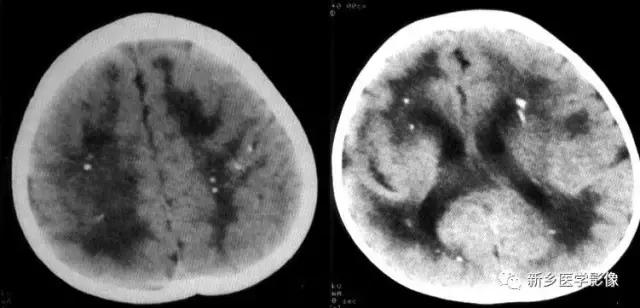

二、脑囊虫病

脑囊虫病慢性期,囊虫死亡以后,囊液逐渐被吸收,囊虫被机化,最后出现钙化。

钙化特点:多发、散在结节样钙化。钙化病灶通常较小、较圆、大小较均匀,少者单发或仅数个,多者可弥漫性分布于全部脑实质。